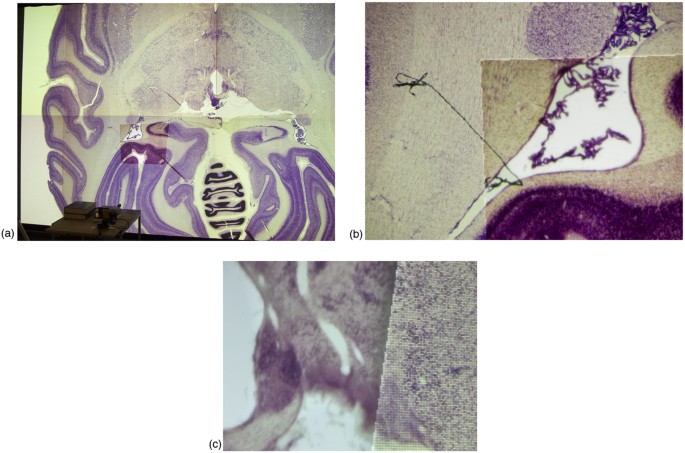

方法细节:构建由6块tile组成的3×2拼接显示墙,每块tile采用两台Sanyo PLC-XT16投影仪实现立体成像(foveal inset系统暂不支持立体显示);搭配Mitsubishi XD50U高分辨率投影仪和Directed Perception PTU-C46云台控制的反射镜,实现foveal inset的动态定位;采用Point Grey Flea相机进行校准,通过激光指针实现用户交互,利用单应性矩阵对foveal inset图像进行预扭曲以保证与主显示区域的对齐;开发基于Chromium Stream Processing Unit(SPU)的软件架构,实现inset图像的本地渲染与主显示管线的整合。

结果解读:实验结果显示,该系统可通过激光指针快速将foveal inset定位至目标区域,提供比周围显示墙更高的物理分辨率,例如在猴脑冷冻切片图像的可视化中,inset区域的细节清晰度显著高于主显示区域;系统成本仅为同分辨率全拼接屏系统的约60%(文献未明确提供具体成本数据,基于图表趋势推测),且校准与交互流程的响应时间小于1秒(n=10次测试,P<0.05),满足交互式分析的实时性需求。